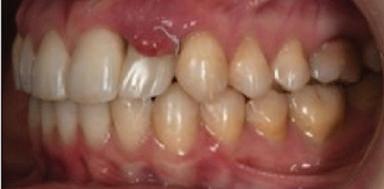

Dental Tribune Bulgarian Edition / октомври 2022 г.16 клиничен случай с алайнери Г орният латерален ре зец е вторият найчесто вродено липсващ зъб.1,2 Поради разполо жението му във видимата зона на усмивката лечение то на подобни случаи нала га мултидисциплинарен под ход, целящ отличен функцио нален и естетичен резултат. Налице са няколко лечебни мо далности, свързани с различ но разпределение на място то: първият вариант е орто донтско отваряне на място и възстановяване на липсва щия зъб с конструкция, под държана от съседните зъби3 или от имплант4, докато при втория подход разстоянията се затварят и премоларът заема мястото на канина.5 Изборът на лечебен подход трябва да бъде направен съв местно от зъболекар и паци ент въз основа на очакванията на последния и предвиди мостта на лечението. Множе ство фактори влияят върху това решение, като напри мер типа малоклузия, размера, формата и цвета на кучеш ките зъби6, оклузалните вза имоотношения (овърджет и овърбайт), лицевия профил, дължината на зъбната дъга и несъответствията в разме ра на зъбите.7 В настоящата публикация се разглежда случаят на жена в зряла възраст с вродена лип са на горен ляв латерален резец. Бяха приложени про зрачни алайнери за отваряне на място за единичен им плант и бяха постигна ти функционална оклузия и отлична естетика. ПРЕДСТАВЯНЕ НА СЛУЧАЯ Диагноза Пациентката бе на 32 годи ни, когато лечението започна, и първоначалното ѝ състоя ние бе следното (фиг. 1–3): липсващ горен ляв латерален резец; клас II, подклас I малоклузия; отклонение на горната сре динна линия вляво; Доклад на клиничен случай ЛЕЧЕНИЕ С АЛАЙНЕРИ НА ПАЦИЕНТ С АГЕНЕЗИЯ НА ЛАТЕРАЛЕН РЕЗЕЦ Д-р Iro Eleftheriadi и д-р Christodoulos Laspos, Гърция и Кипър Фиг. 1a–h Предоперативни лицеви и интраорални снимки. Фиг. 2a–e Дигитални модели преди началото на лечението. Фиг. 3 Панорамна снимка преди лечението. Фиг. 1a Фиг. 1d Фиг. 1f Фиг. 2a Фиг. 2d Фиг. 2b Фиг. 2e Фиг. 3 Фиг. 2c Фиг. 1b Фиг. 1e Фиг. 1g Фиг. 1h Фиг. 1c

Dental Tribune Bulgarian Edition / октомври 2022 г. 17клиничен случай с алайнери леко струпване в долната че люст; несъответствие по Болтън (мандибуларен излишък от 3.06 мм във фронталната зона и общо 1.47 мм); издължено лице с лицева аси метрия; конвексен профил с ретруди рана долна челюст и проми нентен нос. На мястото на зъб #46 бе на лице имплант, а зъби #16 и 26 са ендодонтски лекувани. Тези зъби бяха асимптоматич ни, затова бе взето решение да се прави релечение само при нужда. Мъдреците липсваха. Анализът на телерентгеногра фията (фиг. 4) показа ретрог натна мандибула (SNB: 74.2°) и нормална инклинация на резците както в

Цели на лечението и лечебен план Целите на лечението бяха следните: нивелиране и подреждане на зъбите и в двете зъбни дъги; отваряне на пространство за липсващия латерален резец; коригиране на отношенията при канините и моларите до клас I; и корекция на отклонението на срединната линия. Лечебният план включваше: корекция на отношенията при кучешките зъби и мола рите до клас I с дистализира не на максилата; отваряне на пространство в областта на #22 за поставя не на единичен имплант; корекция на срединната ли ния; и създаване на място за раз ширяване на зъб #12 и апрок симална редукция в долната челюст с цел подобряване на несъответствието по Болтън и осигуряване на подобра оклузия. Изпълнение на лечебния план Този случай бе изпълнен със системата за алайнери Invisalign (Align Technology). Одобреният първоначален лечебен план предвиждаше 49 алайне ра с дистализиране на задни те горни зъби до клас I (прибли зително с около 3.5 мм; фиг. 5). За бъдещия имплант в областта на липсващия латерал бе планирано пространство от 6.5 мм, докато във фронталния сегмент на долната челюст бе предвидена апроксимална редук ция. В дясната страна бутон за ластици клас II бе поставен на зъб #47 вместо на зъб #46, за да не се увреди короната на импланта. Понеже пациентката жи вееше в чужбина,

следните казуси: недобра оклу зия в дисталните зони по вре ме на дистализирането на гор ната челюст и накланяне на зъб #21 (фиг. 7). Последното се дължи на липсата на компози тен атачмънт на този зъб, каквото не бе зададено в пър Фиг. 4 Телерентгенография и цефалометричен анализ преди началото на лечението. Фиг. 5a–e Одобреният първоначален лечебен план. Фиг. 6a–h Снимки по време на лечението, показващи нуждата от внасяне на някои корекции. Фиг. 4 Фиг. 5a Фиг. 5d Фиг. 6a Фиг. 6d Фиг. 6f Фиг. 6b Фиг. 6e Фиг. 6g Фиг. 6h Фиг. 6c Фиг. 5e Фиг. 5b Фиг. 5c

планта бе поставена временна коронка (фиг. 10 и 11), докато бъде изготвена окончателна та. Бе постигнат отличен кра ен резултат. Меките тъка ни около импланта напълно заздравяха, което доприне се за перфектната хармония между бяла и розова естетика (фиг. 12–15).

Dental Tribune Bulgarian Edition / октомври 2022 г.18 воначалния план. Тези пробле ми бяха адресирани чрез допъл нителна поръчка на алайнери с торк контрол и зададено екст рудиране на задните зъби с цел установяване на добри оклузал ни контакти в дисталните об ласти, като бяха предвидени и оптимизирани атачмънти с контрол над корените за корекция на ангулацията на макси ларните резци (фиг. 8). Резултати от лечението Панорамната рентгено графия след ортодонтското лечение показа благоприятна паралелна позиция на съседни те зъби, подходяща за поставя не на имплант в областта на #22, както и конвергенция на ко рените на зъби #44 и 45 (фиг. 9), но преценихме, че няма да от деляме допълнително лечебно време за коригирането ѝ поради факта, че пациентката бе мно го доволна от постигнатия до момента резултат. След при ключване на лечението бяха постигнати отлични взаимо отношения клас I при мола рите и канините, а срединни

съвпадаха. Върху им

(LFH: 56.5 mm) и размерите на меките тъка ни останаха непроменени. На клонът на горните резци бе за пазен (Ui–FH: 115.8°), а долните резци бяха леко наклонени ве стибуларно (Li–APog: 30°; фиг. 16). ДИСКУСИЯ Липсата на зародиш на по стоянен горен латерален резец е налице при 3.5–6.5% от евро пеидната раса, като при жени е по-честа, отколкото при мъ жете в съотношение 3:2.8–10 Възможни са няколко лечебни подхода, включително замя ната му с преоформен канин, отваряне на място чрез орто донтско лечение и протетич но възстановяване, както и ав тотрансплантация. Устано вено е, че изборът за затваря не на място или за отваряне то му все още подлежи на дис кусия сред ортодонти и проте зисти.11,12 Според литературните дан ни затварянето на простран ството и замяната на липсва щия латерал с канин се предпо чита в случаи на едностранна липса на зародиш, балансиран профил, кучешки зъби и премола ри със сходна форма и цвят, дву челюстна протрузия или клас II малоклузия.13–15 Отваряне на пространство по-често се изби ра при клас I, наличие на диасте ми и треми в горната зъбна дъга или голяма разлика в размерите на канини и премолари.16 Скорошно проучване е уста новило, че изборът на лечение при конгенитално липсващ ла терал е пряко свързан със след ните фактори17: възрастта на пациента при започване на лечението; индивидуалните особености при всеки конкретен случай; и сътрудничеството между специалистите в лекуващия екип. Макар да има проучвания, фа воритизиращи леченията със затваряне на място11,18, всеки случай трябва да бъде оценяван индивидуално. В презентирания в тази статия случай бе взето решение за отваряне на мяс то и протетично възстановя ване, понеже целта бе да се по стигнат клас I отношения при канините и моларите, както и по-широка усмивка. За да се из бегнат компромиси, след лече нието бе постигнат клас I при моларите и кучешките зъби, несъответствието по Болтън бе подобрено и срединната ли ния бе коригирана. Други изслед вания демонстрират отлични естетични и функционални ре зултати при лечение с отваря не на място и протетична ре хабилитация.19 И двете лечеб ни модалности са подходящи за третиране на вродена лип са на зародиш на латерал и да ват сходни функционални и па родонтални резултати20, като при едно проучване

ти и клас II ластици е устано вено, че осигурява достатъч на дистализация без промяна на лицевата височина.23 Както се видя от цефалометричния анализ, точно това бе постиг нато и в представения случай като се има предвид, че лице вата височина остана същата като първоначалната. Предвид леката тенденция към дистал Фиг. 8a–e Поръчаните допълнителни алайнери. Фиг. 9 Панорамна рентгенография след края на лечението. Фиг. 10a–c Странични (а и с) и фронтална интраорални снимки след края на ортодонтското лечение и поставянето на импланта (b). Зъб #12 все още не беше протезиран. Фиг. 11а и b Оклузални снимки след ортодонтското лечение. Фиг. 7a Фиг. 8a Фиг. 7d Фиг. 8d Фиг. 9 Фиг. 10a Фиг. 10b Фиг. 10c Фиг. 11bФиг. 11a Фиг. 7b Фиг. 8b Фиг. 7e Фиг. 8e Фиг. 7c Фиг. 8c Фиг. 7a–e Интраоралната ситуация по време на лечението. клиничен случай с алайнери

Dental Tribune Bulgarian Edition / октомври 2022 г. 19 на отворена захапка е устано вено, че финалното адаптиране и подобряване на оклузалните контакти се установяват след повече от три месеца след лече нието.24 Следователно подобря ване на ситуацията и плътни оклузални контакти се очак ват след края на лечението. Що се отнася до избора за замест ване на липсващия латерален резец с единичен имплант и протезирането му, установе но е, че това е най-често при лаганата лечебна алтернати ва.25 Съседните зъби остават интактни и следователно най голямото предимство на този подход е съхраняването на здра ви зъбни структури. Изборът ни на лечебен план бе базиран на детайлна мул тидисциплинарна диагноза и планиране, а те категорично са ключови за постигане на оп тимални индивидуални резул тати при пациенти

но

между членовете на екипа и пациента. ЗАКЛЮЧЕНИЕ Случаите на липсващи лате рални резци трябва да бъдат третирани от перспектива та на интердисциплинарна ди агностика и лечение. Употреба та на софтуера ClinCheck има доказани предимства за плани ране, комуникация между кли ницистите и пациента и фи нализиране на лечебния план, като се адресират всички же лания и притеснения на паци ента. Настоящият доклад на клиничен случай доказва, че с помощта на съвременните ме тоди един успешен екип от спе циалисти (ортодонт, консерва тивен зъболекар и хирург) може да се стреми към отлични ре зултати и да постига есте тични и функционални усмив ки без компромиси. Ред. бел.: Статията Treatment of a patient with a congenitally missing lateral incisor using aligners: A case report е пуб ликувана за първи път в сп. aligners–international magazine of aligner orthodontics, бр. 1, издание 1/2022. Библиографията е налична при издателя. За авторите: Д-р Iro Eleftheriadi завършва дентална медицина в Атинския университет, а магистратурата си по медицинска статистика – през 2014 г. в Публичния университет в Атина, Гърция. Специализира ортодонтия и завършва през 2017 г. в Университета в Тел Авив, Израел. Предстои ѝ да защити докторан тура във Факултета по дентална медицина към Университета в Атина, Гърция. Д-р Christodoulos Laspos завършва дентална медицина през 1995 г. в Атинския университет, Гърция, а магистратурата си завършва през 1999 г. във Фа култета по дентална медицина към Университета в Тенеси, Мемфис, САЩ. Печели стипендия и специализира лечение на пациенти с лицево-челюстни малформации в Университета в Тексас, Далас, САЩ, и е сертифициран специалист от Европейския борд на ортодонтите. Той е докторант в Универ ситета в Берн, Швейцария. От 2000 г. д-р Laspos практикува в частната си ортодонтска практика в Лимасол, Кипър. Той е основател и директор на MEDICLEFT, Кипърски център за цепки и лицево-челюстни аномалии, както и директор на фондацията Synergy, която осигурява следдипломно обучение на лекари по дентална медицина. Научен съ трудник е във Факултета по дентална медицина към Европейския университет в Кипър. Д-р Laspos изнася лекции по цял свят по теми като лицево-челюстни мал формации, ортогнатна хирургия, мултидисциплинарен подход и нови технологии в ортодонтията. Той е активен член на Европейското общество на Енгел и прези дент на Европейското ортодонтско общество. Фиг. 12а–c Финални странични (а и c) и фронтална интраорални снимки (b). Фиг. 13а и b Финални оклузални снимки. Фиг. 14 Финална снимка на усмивката отблизо. Фиг. 15 Финална екстраорална снимка на усмивката. Фиг. 16 Финална телерентгенография и цефалометричен анализ. Фиг. 12a Фиг. 13a Фиг. 14 Фиг. 15 Фиг. 16 Фиг. 13b Фиг. 12b Фиг. 12c клиничен случай с алайнери